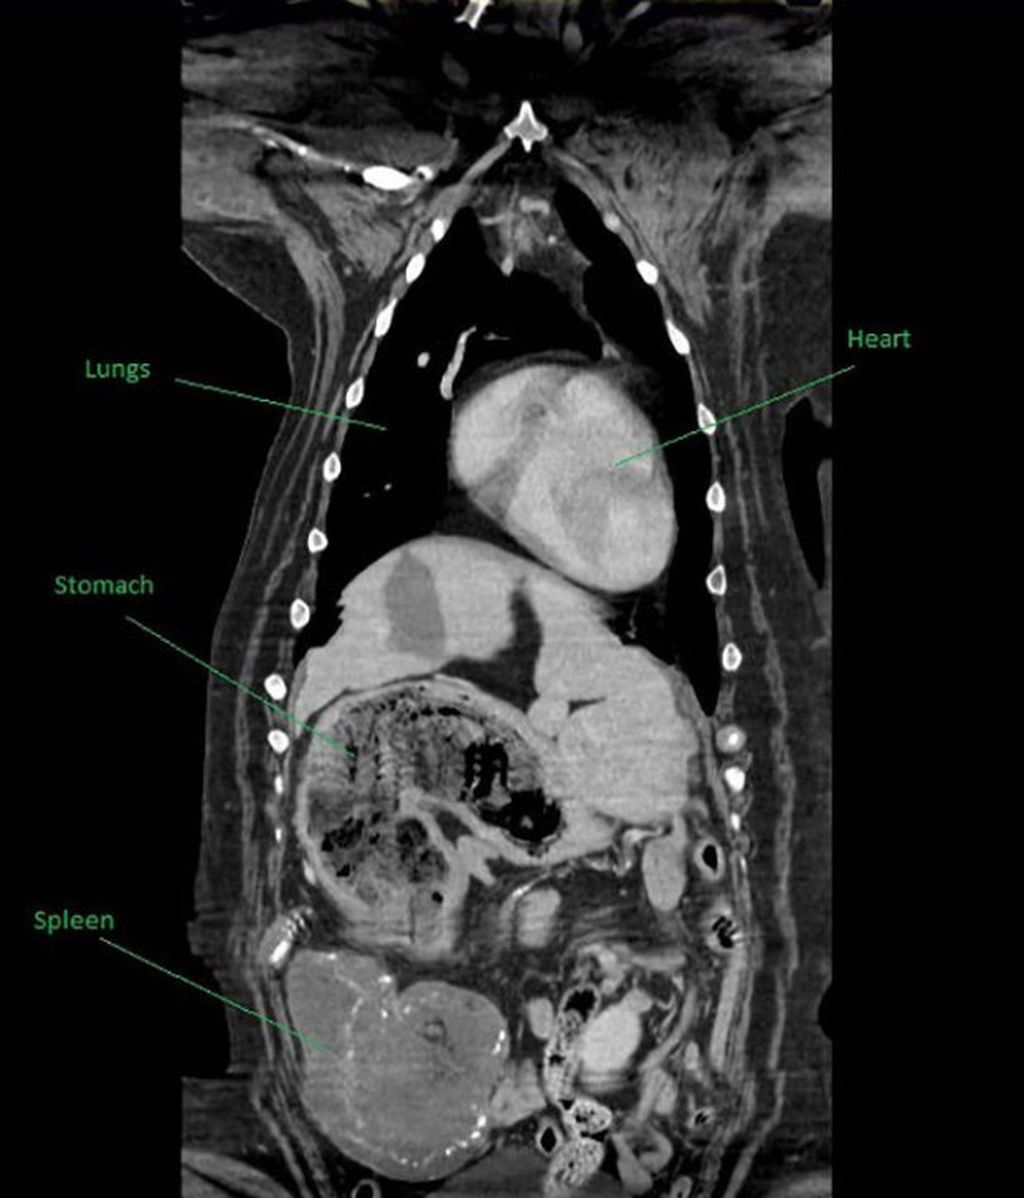

Los primeros escaneos en el abdomen de Maisy habían mostrado que tenía el estómago lleno y una masa extraña en el bazo, lo que los veterinarios atribuyeron en un primer momento a un problema con su comida, la cual creían que no digería adecuadamente, según sostiene Metro.